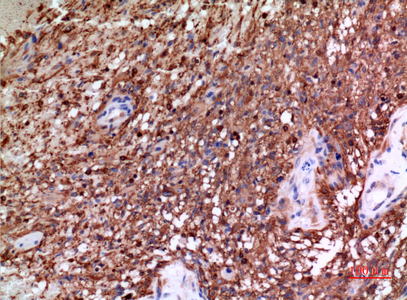

Main InformationTargetTubulin αHost SpeciesRabbitReactivityHuman, Mouse, RatApplicationsWB, IHC, IF, ELISAMW50kD (Observed)Conjugate/ModificationUnmodifiedDetailed InformationRecommended Dilution RatioWB 1:500-1:2000; IHC: 1:100-1:300; ELISA 1:20000; IF 1:50-200FormulationLiquid in PBS containing 50% glycerol, 0.5% BSA and 0.02% sodium azide.SpecificityTubulin α Polyclonal Antibody detects endogenous levels of Tubulin α protein.PurificationThe antibody was affinity-purified from rabbit antiserum by affinity-chromatography using epitope-specific immunogen.Storage-15°C to -25°C/1 year(Do not lower than -25°C)Concentration1 mg/mlMW(Observed)50kDModificationUnmodifiedClonalityPolyclonalIsotypeIgGAntigen&Target InformationImmunogen:The antiserum was produced against synthesized peptide derived from human TUBA1A around the non-acetylation site of Lys40. AA range:1-50Specificity:Tubulin α Polyclonal Antibody detects endogenous levels of Tubulin α protein.Gene Name:TUBA1A/TUBA1B/TUBA1C/TUBA3C/TUBA4AProtein Name:Tubulin alpha-1A chain/Tubulin alpha-1B chain/Tubulin alpha-1C chain/Tubulin alpha-3C/D chain/Tubulin alpha-4A chainOther Name:TUBA1A ; TUBA3 ; Tubulin alpha-1A chain ; Alpha-tubulin 3 ; Tubulin B-alpha-1 ; Tubulin alpha-3 chain ; TUBA1B ; Tubulin alpha-1B chain ; Alpha-tubulin ubiquitous ; Tubulin K-alpha-1 ; Tubulin alpha-ubiquitous chain ; TUBA1C ; TUBA6 ; Tubulin alpha-1C chain ; Alpha-tubulin 6 ; Tubulin alpha-6 chain ; TUBA3C ; TUBA2 ; TUBA3D ; Tubulin alpha-3C/D chain ; Alpha-tubulin 2 ; Alpha-tubulin 3C/D ; Tubulin alpha-2 chain ; TUBA4A ; TUBA1 ; Tubulin alpha-4A chain ; Alpha-tubulin 1 ;Database Link:Background:Microtubules of the eukaryotic cytoskeleton perform essential and diverse functions and are composed of a heterodimer of alpha and beta tubulins. The genes encoding these microtubule constituents belong to the tubulin superfamily, which is composed of six distinct families. Genes from the alpha, beta and gamma tubulin families are found in all eukaryotes. The alpha and beta tubulins represent the major components of microtubules, while gamma tubulin plays a critical role in the nucleation of microtubule assembly. There are multiple alpha and beta tubulin genes, which are highly conserved among species. This gene encodes alpha tubulin and is highly similar to the mouse and rat Tuba1 genes. Northern blotting studies have shown that the gene expression is predominantly found in morphologically differentiated neurologic cells. This gene is one of three alpha-tubulin genes in a cluster on chromosome 12q.Function:Disease:Defects in TUBA1A are the cause of lissencephaly type 3 (LIS3) [MIM:611603]. LIS is characterized by a smooth brain surface due to the absence (agyria) or reduction (pachygyria) of surface convolutions. It is often associated with psychomotor retardation and seizures. LIS3 features include agyria or pachygyria or laminar heterotopia, severe mental retardation, motor delay, variable presence of seizures, and abnormalities of corpus callosum, hippocampus, cerebellar vermis and brainstem.,Function:Tubulin is the major constituent of microtubules. It binds two moles of GTP, one at an exchangeable site on the beta chain and one at a non-exchangeable site on the alpha-chain.,PTM:Undergoes a tyrosination/detyrosination cycle, the cyclic removal and re-addition of a C-terminal tyrosine residue by the enzymes tubulin tyrosine carboxypeptidase (TTCP) and tubulin tyrosine ligase (TTL), respectively.,similarity:Belongs to the tubulin family.,subunit:Dimer of alpha and beta chains.,tissue specificity:Expressed at a high level in fetal brain.,Cellular Localization:Cytoplasm, cytoskeleton.Tissue Expression:Expressed at a high level in fetal brain.Research Areas:>>Phagosome ; >>Apoptosis ; >>Tight junction ; >>Gap junction ; >>Alzheimer disease ; >>Parkinson disease ; >>Amyotrophic lateral sclerosis ; >>Huntington disease ; >>Prion disease ; >>Pathways of neurodegeneration - multiple diseases ; >>Pathogenic Escherichia coli infection ; >>Salmonella infection